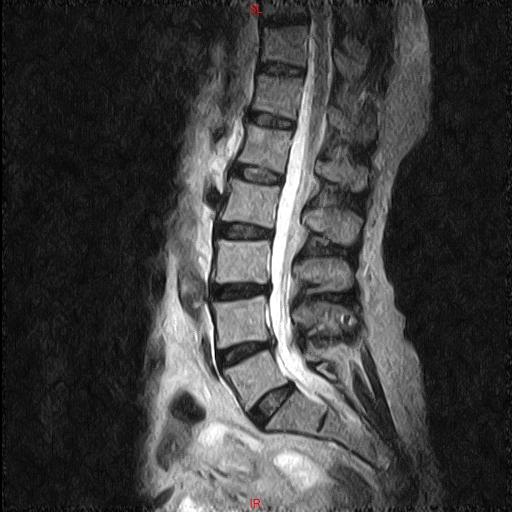

• RESONANCIA PATOLÓGICA DE C.LUMBAR - HERNIA DE DISCO L5-S1 -  SAG T2